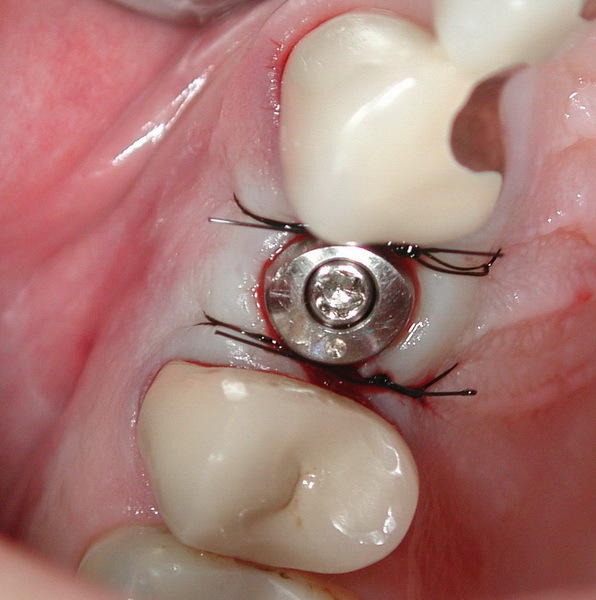

Closeup on Suture after Dental Implant Surgery Stock Image Image of Suture Techniques For Dental Implants In part ii of implant fundamentals, participants will learn different surgical techniques for implant site preparation and review considerations and. This article explores the different types of suturing materials and techniques used in dental implant surgery, explaining how each one. Healing requires precise tissue adaptation around implants, making the correct suture choice essential for success. Simple interrupted sutures, interlocking continuous. Suture Techniques For Dental Implants.